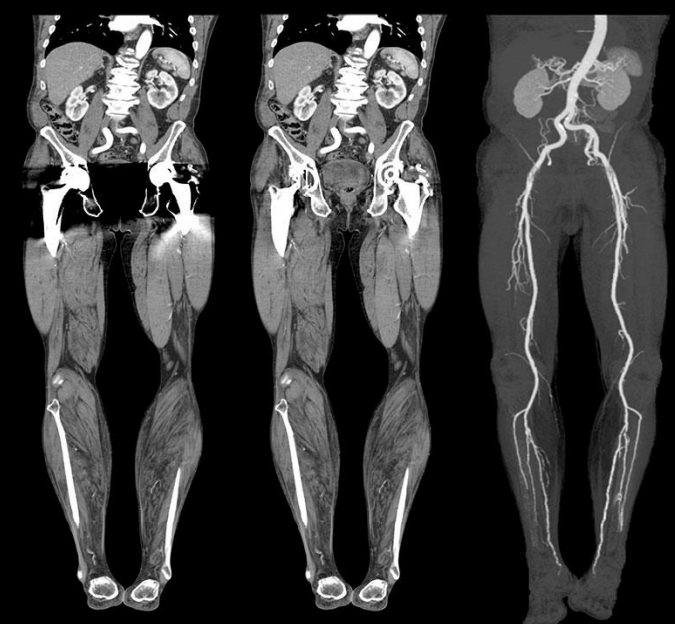

Angio TC arterial, Angio TC venosa – Algumas Indicações: isquemia arterial, trombose venosa profunda.

A maior indicação para a angiotomografia de membro superior e inferior é a avaliação de obstruções arteriais (por tromboses ou estreitamentos), embora algumas tromboses venosas também possam ser diagnosticadas. Podem ser realizadas reconstruções multiplanares e em 3D.